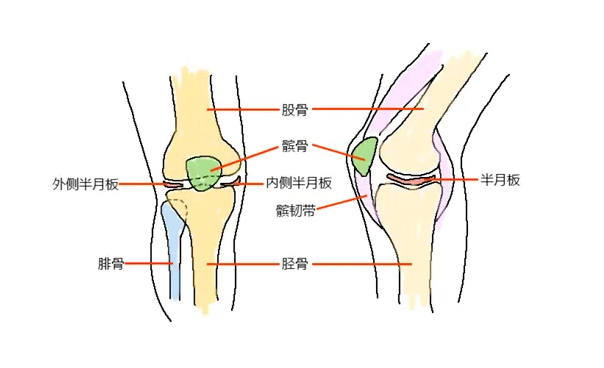

关节的寿命是有限的。一旦关节“气数已尽”,就会引发各种关节病! 关节的寿命主要是由基因决定的,一般的健康寿命是 60 年,过度使用会加重对它的磨损,并且不可修复。

还有一个更扎心的事实是女性的膝关节天生不完美,一项对中国膝关节骨关节炎的患病率及危险因素进行的大样本调查发现,我国膝关节炎发病率女性为 10.3%,男性为 5.7%,女性明显高于男性。

我国约有 1.2 亿人患有骨关节炎:

50 岁以上,约 50% 被膝骨关节炎困扰

60 岁后患病率达 60%

70 岁以上,几乎每个老年人都会患此病

无论男女都应该保养膝盖,尤其是 30 岁以后。

在瑜伽练习中,除了通过这些体式来保护膝关节,我们一定要注意,在屈膝的时候,膝盖不要超过脚趾尖,并且要注意膝关节的正位,也即是膝盖要指向第 2、3 个脚趾尖的方向。

在生活中,也要多注意保护膝关节,避免膝关节受凉、注意运动的安全性、减少负重次数和时间等。